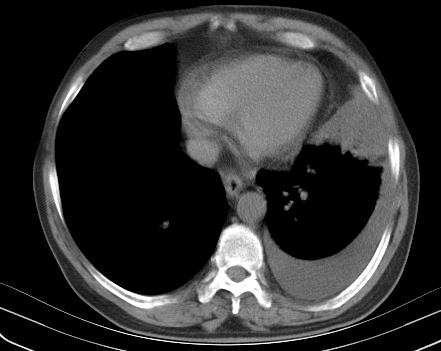

以下是引用老爱克斯新网客在2008-7-31 6:30:00的发言:[br]左肺上叶大片状病灶,左肺上叶支气管狭窄呈鼠尾状,左肺门增大,纵隔内见肿大淋巴结,左侧胸腔积液,余肺清晰。左肺中心型肺癌淋巴结转移,

以下是引用zjzjr在2008-7-31 8:45:00的发言:[br]考虑左侧中心性肺癌伴阻塞性肺炎,左肺上叶肺不张,纵隔淋巴结转移;左侧胸腔积液。建议行纤支镜检查。

以下是引用zjb在2008-7-31 6:32:00的发言:[br]左侧中心性肺癌 阻塞性肺炎 肺不张 胸腔积液 建议气管镜

以下是引用sdzyy在2008-7-31 8:47:00的发言:[br]病灶较治疗前有所进展,胸水增多, 左侧中心性肺癌 并 阻塞性肺炎 肺不张 胸腔积液 可能性大; 建议气管镜检查。 [br] [br]